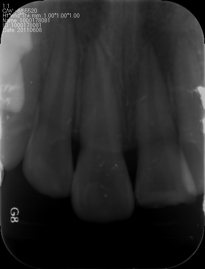

检查:21牙冠缺损,断面见护髓材料,牙冠色暗,探诊不敏感,叩痛(+++),IO松动,唇侧根方可扪及脓肿,扪痛明显,有波动感,未见瘘管,冷测迟钝 X线片见21牙根完整,见根尖周低密度影,边界不清 21,22牙冠完整,叩痛(+),I松动,牙龈未见明显异常,冷测正常